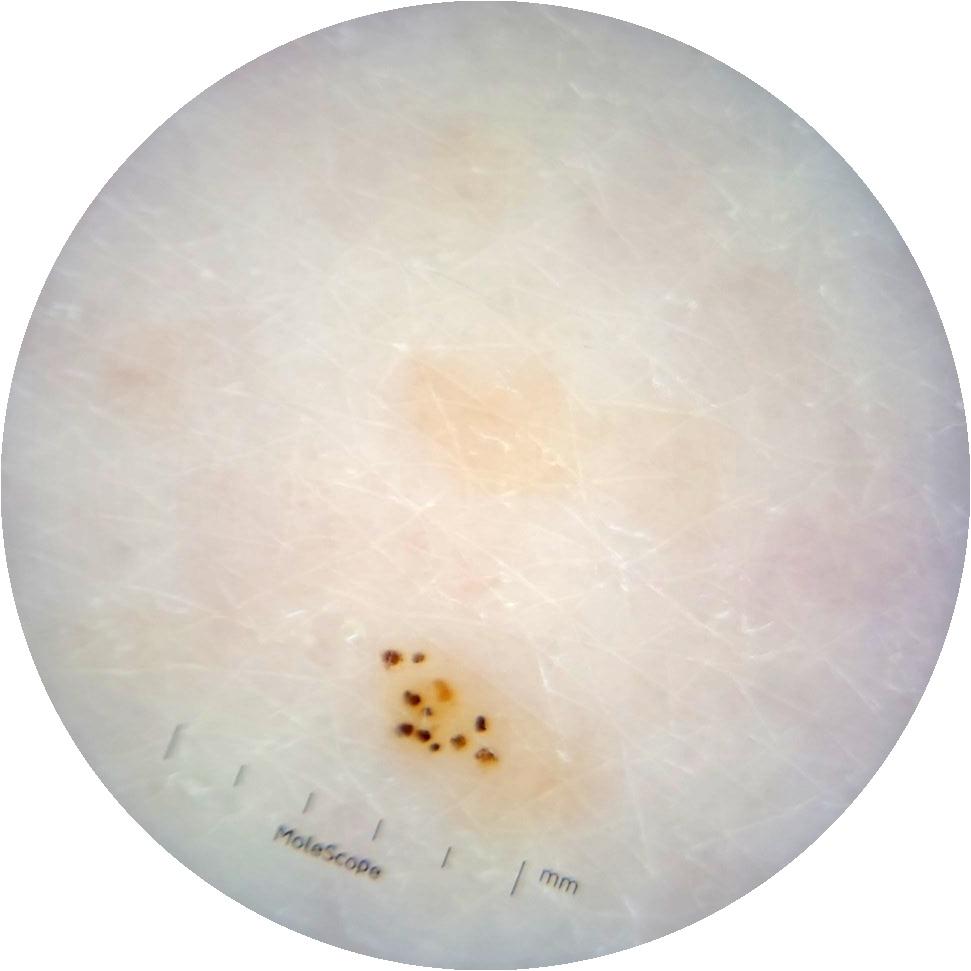

Clinical

Field Value

acquisition_day 264

age_approx 65

anatom_site_1 Trunk

anatom_site_2 Anterior trunk

anatom_site_general anterior torso

diagnosis_1 Benign

diagnosis_confirm_type single image expert consensus

image_type dermoscopic